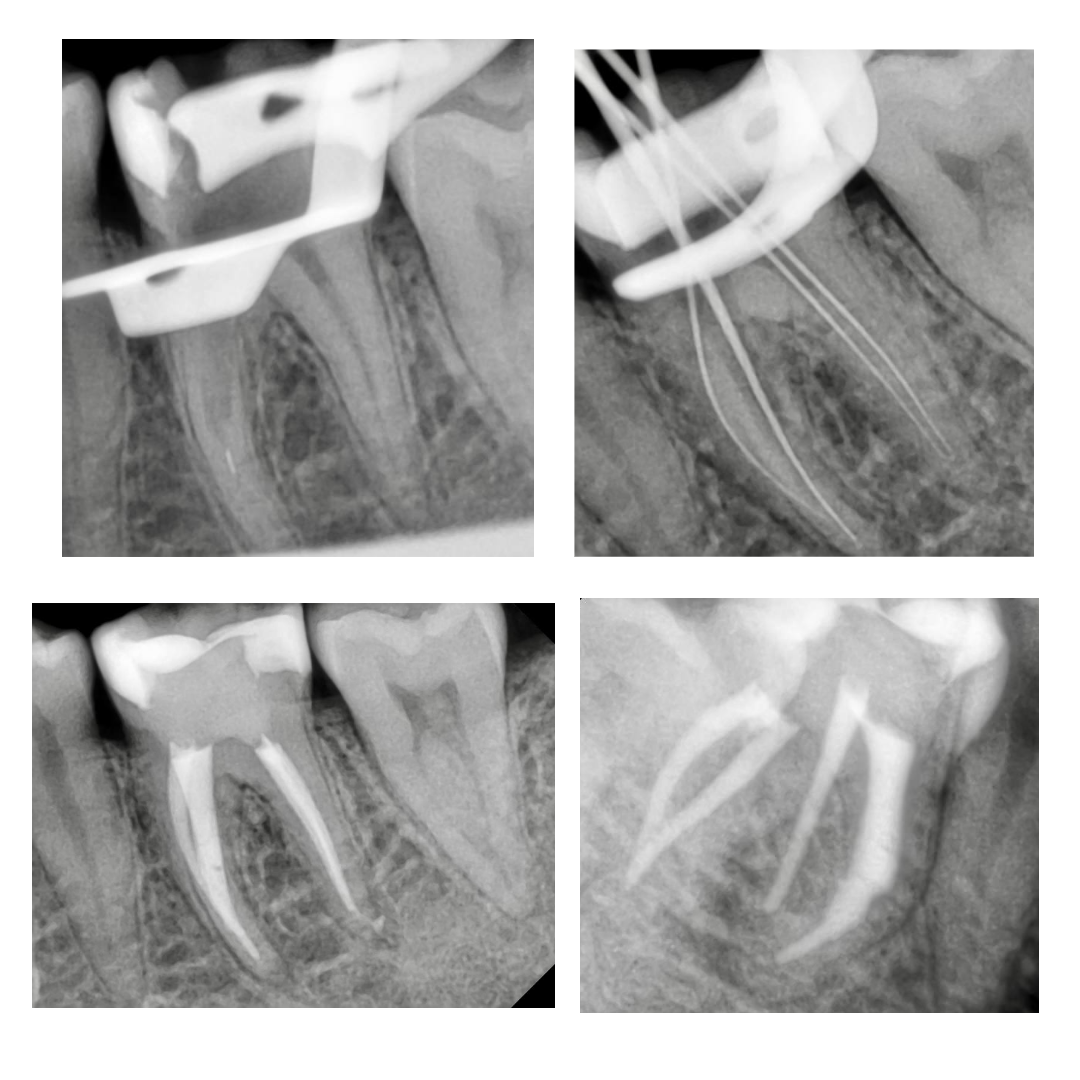

Случай, который демонстрирует, что доставать фрагмент инструмента без увеличения - плохая идея.

Попытки самостоятельно достать фрагмент привели к перерасширению.

Два визита: первый извлечение, второй завершение работы.